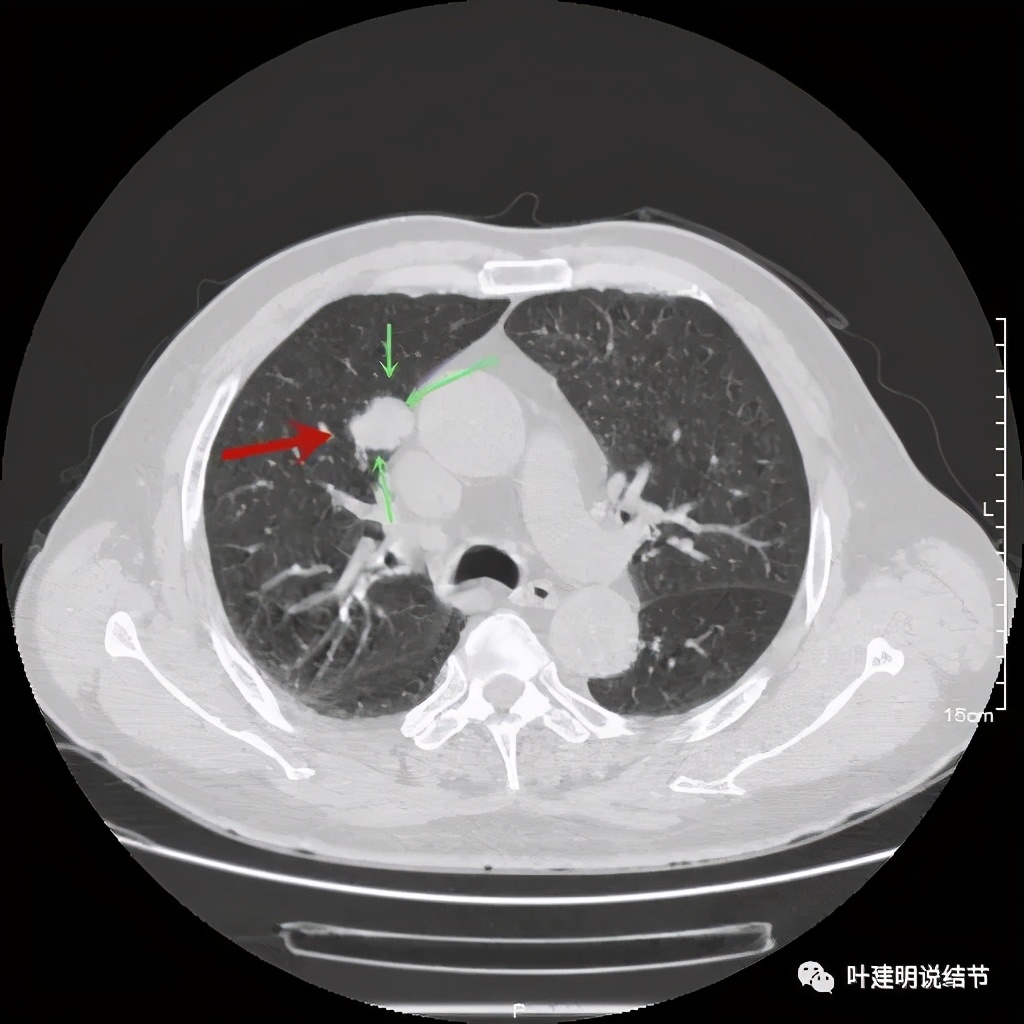

直径约2.4厘米,密度欠均,血管贴边,增强轻度强化。单从描述看,恶性可能性较大。我们再来看看图像:

可见右上叶占位,我们现在知道了结果以后回头看,发现病灶的边缘在各个层面都是过于光滑(绿色箭头所示)。血管紧贴病灶边走行(桔色箭头所指),是不是有侵犯看不清楚,若是靶扫描加重建可能会更清楚点。支气管感觉也是贴着病灶走,但有的层面是不是截断,也不看的不太清楚。有的层面见局部有点状高密度(蓝色箭头所指),是不是错构瘤的局部钙化呢?若是纵隔窗又是如何?

上图示病灶

上图示病灶密度不均